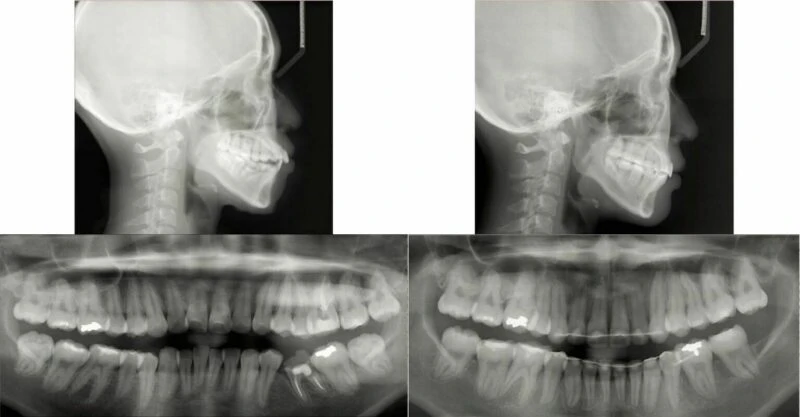

Hình 7 Phim toàn cảnh và phim đo sọ trước điều trị cho thấy môi căng, mất răng 35 và răng 36 điều trị tuỷ không tốt